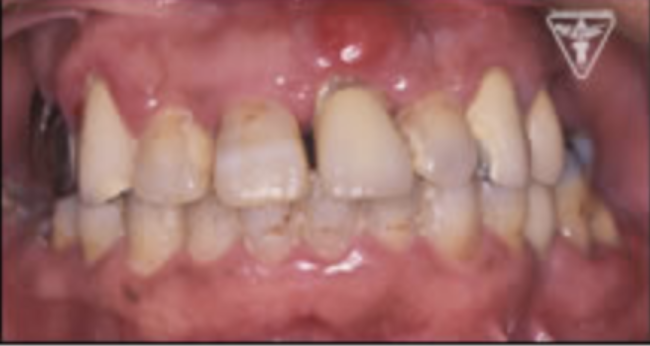

治療前

初診時での正面・側方・咬合面観を示します。